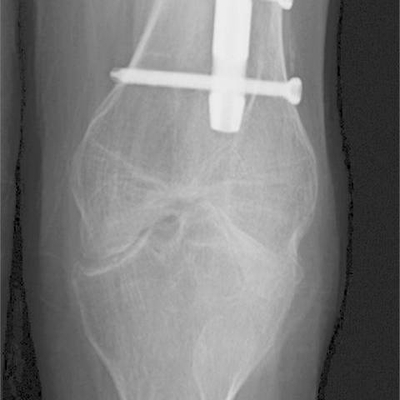

Click on an image below to view more info.